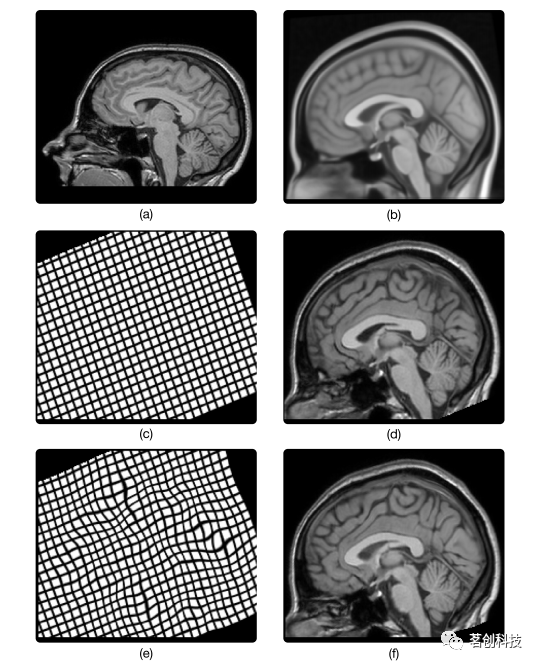

被试之间的应用通常需要使用非刚性图像配准来校正被试之间的大小和形状的显著差异。特别地,采用非刚性线性图像配准来匹配图像的全局形状和大小,以及位置和方向;示例如图2c所示。然后应用可变形图像配准来匹配局部形状和大小;示例如图2e所示。一些被试内的应用也需要非刚性图像配准。一个重要的例子是对扩散MRI中涡流引起的几何畸变校正。由扩散敏感梯度产生的涡流会导致所获得的图像产生几何畸变。事实证明,这种几何畸变可以很好地近似为非刚性线性变换。因此,采用非刚性线性图像配准方法对其进行校正。此外,非刚性线性变换的形式在很大程度上取决于扩散敏感梯度的性质。一些技术利用这种关系来产生所需线性变换的高质量初始猜测。另一个例子是回波平面成像(EPI)中由磁化率引起的几何畸变校正。软组织与骨骼或空气界面之间的敏感性差异会导致高度局部化、非线性、几何畸变。在没有任何附加信息的情况下,例如在其他方面都相同的采集过程中,但EPI相位编码方向相反,可以通过将EPI图像与同一个体的T1加权扫描进行非线性图像配准来校正几何畸变。

图2.被试间配准的空间标准化示意图。图(a)显示了一个健康被试的T1加权(T1w) MRI脑部扫描。图(b)显示了蒙特利尔神经研究所(MNI)通过对152名健康被试的平均脑MRI扫描而开发的MNI152 T1w模板。应用被试间配准使T1w扫描与MNI152模板对齐。这涉及到首先应用线性配准来找到线性变换,使T1w扫描在大小和形状上与模板大致相似。由此产生的线性变换及其在规则网格上的作用如图(c)所示。这种变换对T1w扫描的影响如图(d)所示。在线性配准之后,应用非线性配准来找到一个非线性变换,以将T1w扫描与模板详细匹配。图(e)将产生的非线性变换可视化。图(f)显示了应用此变换后的T1w扫描,该扫描现在相对于模板定义的标准空间进行了空间标准化。